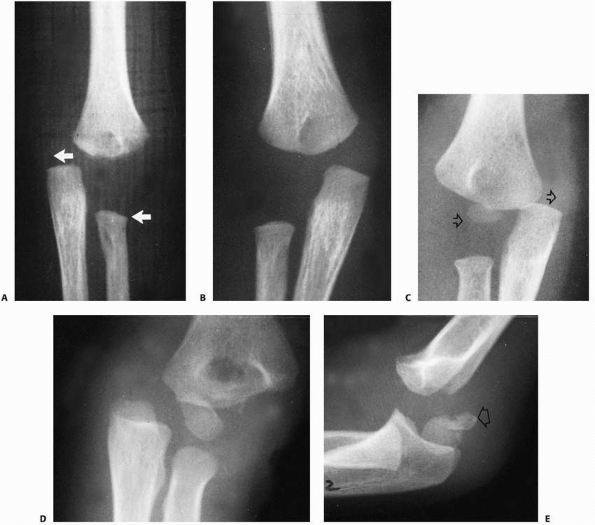

![]() |

FIGURE 15-1 A. Injury film of a 7-year-old with an undisplaced fracture of the lateral condyle (small arrows). Attention was drawn to the location of the fracture because of extensive soft tissue swelling on the lateral aspect (white arrows). B.

Because of the extensive soft tissue injury, there was little intrinsic stability, allowing the fracture to become displaced at 7 days (arrow). |